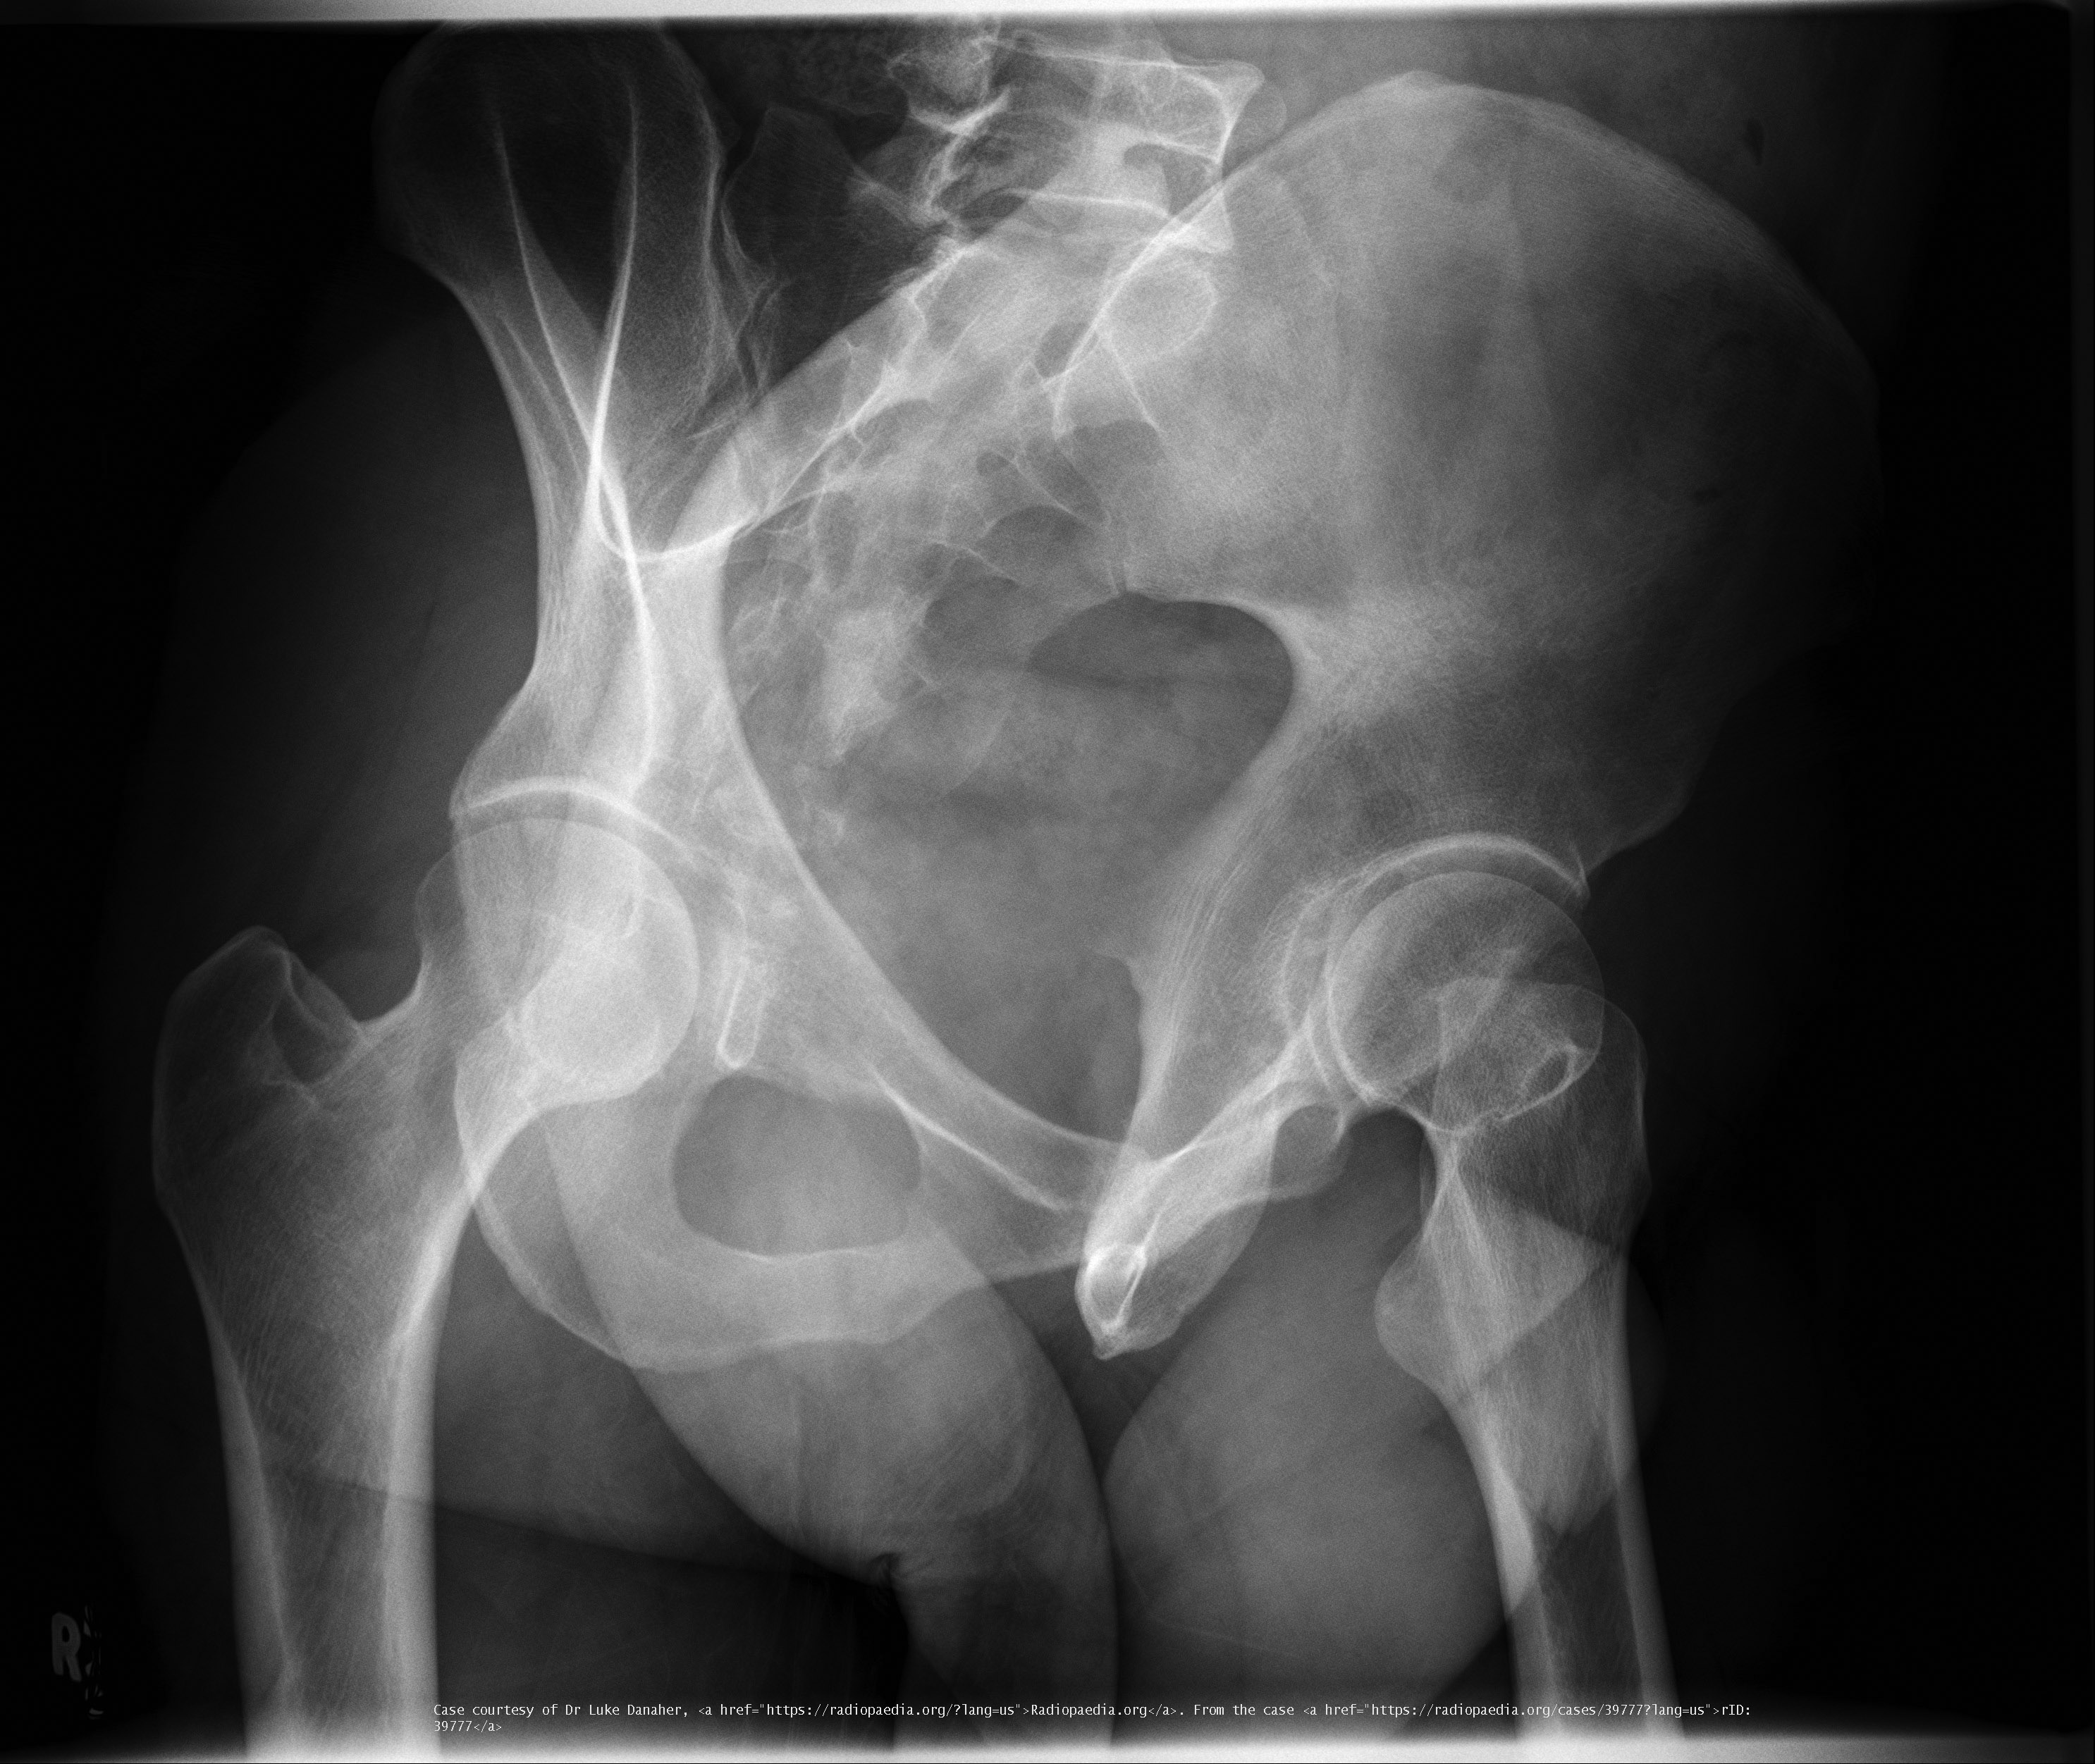

What are Judet views used for?

Evaluation of acetabular fractures.

<p>Evaluation of acetabular fractures.</p>

What is the degree of obliquity for Judet views?

45°.

Why are Judet views performed in trauma cases?

To assess column involvement in acetabular fractures.